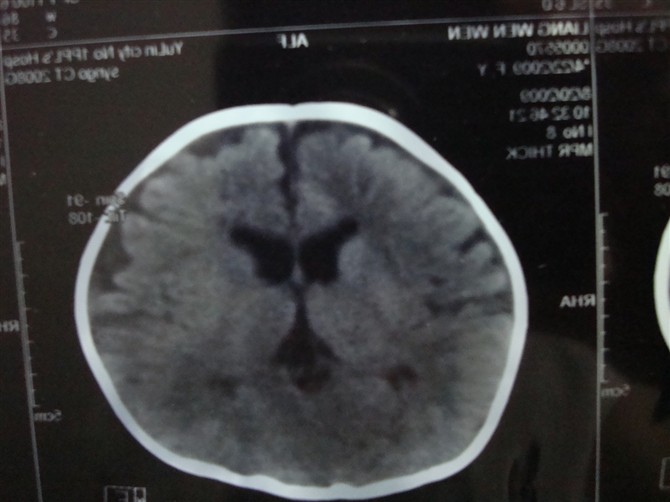

考虑外部性脑积水。

胼胝体发育不良,外部性脑积水。脑白质密度减低,hie后遗症?

蛛网膜囊肿

未见明显异常.

图像不连续,外部性脑积水诊断问题不大,另外,三脑室上抬,侧脑室间距增宽,支持考虑胼胝体发育不良。